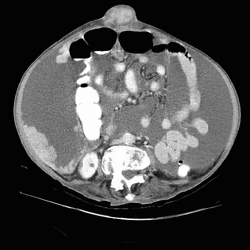

RADIOLOGY: ABDOMEN: Case# 33027: CARCINOMATOSIS. 80 year old female with history of umbilical herniorraphy and abdominal distention. 1) Large amount of ascites with multiple peritoneal based masses as described above. The appearance is consistent with peritoneal carcinomatosis from an as yet undetermined source. The differential diagnosis would include ovarian carcinoma, adenocarcinoma of the gastrointestinal tract, carcinoma of the breast, and renal cell carcinoma. There is apparent metastasis to the umbilical hernia site as well as to a 2 cm right inguinal node. 2) Small bilateral pleural effusions, right greater than left. 3) Simple left renal cyst.